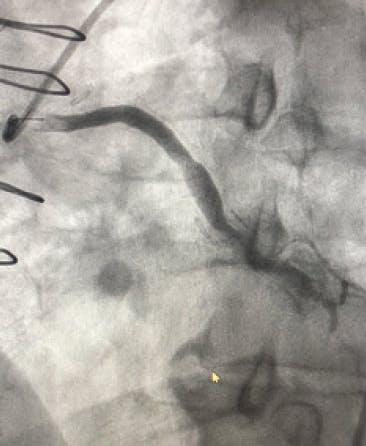

A 2-mm balloon was used to perform the Dotter technique to predilate the vessel (Figure 1). Heavy thrombus burden was visualized angiographically, and it was decided that mechanical thrombectomy with CAT RX would be introduced (Figure 2). After multiple passes of CAT RX with 30 seconds of aspiration each, there was improved flow through the vessel (Figure 3). Then, 4- X 38-mm and 4- X 32-mm drug-eluting stents (DESs) were placed distally and in the midbody, resulting in thrombolysis in myocardial infarction (TIMI) 3 flow (Figure 4).

Figure 1. An angiogram shows an occluded right coronary artery (RCA).

Figure 2. Heavy thrombus burden was visualized angiographically after using the Dotter technique.

Figure 3. Improved flow through the vessel after using CAT RX.

Figure 4. TIMI 3 flow achieved.